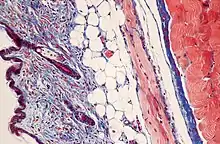

Masson's trichrome is a three-colour staining procedure used in histology. The recipes evolved from Claude L. Pierre Masson's (1880–1959) original formulation have different specific applications, but all are suited for distinguishing cells from surrounding connective tissue.

Most recipes produce red keratin and muscle fibers, blue or green collagen and bone, light red or pink cytoplasm, and dark brown to black cell nuclei.

Standard applications: Masson's trichrome staining is widely used to study muscular pathologies (muscular dystrophy), cardiac pathologies (infarct), hepatic pathologies (cirrhosis) or kidney pathologies (glomerular fibrosis). It can also be used to detect and analyze tumors on hepatic and kidney biopsies.[1]